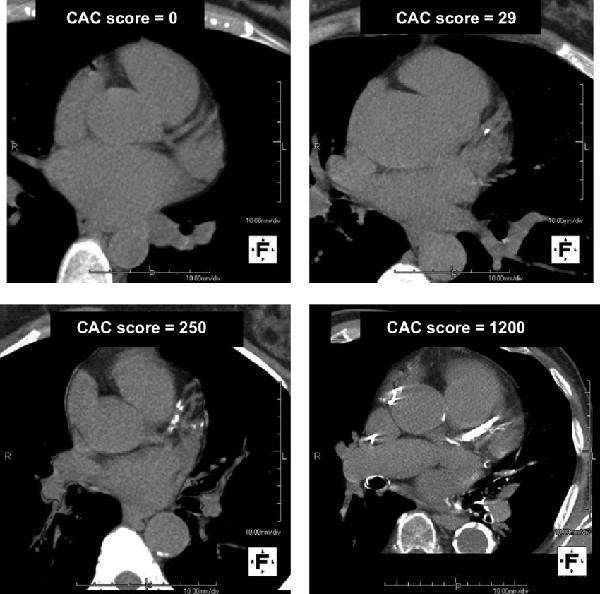

- สามารถประเมินแคลเซียมในเส้นเลือดหัวใจ (Calcium score) เพื่อคัดกรองความเสี่ยงได้ (ไม่ต้องฉีดสี)

| ดูหินปูนเกาะเส้นเลือด |

⭐⭐⭐ ทำได้ |